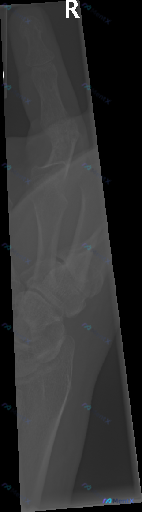

- 影像:右手指(可能是拇指)侧位X光片,视野偏局限,主要显示近节指骨、掌指关节区和部分掌骨头

- 原始影像报告描述:骨皮质连续,骨小梁清晰,掌指关节对位良好,关节间隙均匀,未见明显骨折、脱位、骨质破坏或高密度异物

- 关键前提:这份资料明确提示「存在异常」

报告看起来很「正常」,但前提却说有问题。如果只看报告可能就放过去了,但结合这个前提,你第一反应会往哪些方向考虑?最容易漏诊的是什么?